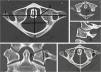

Materials and methodsDimensions of the atlas were measured on 200 CT scans of the craniocervical junction in individuals aged 0–18 years and on 34 anatomical specimens of the first cervical vertebra (aged 2.5–18 years). Both series were divided according to the gender and age. The values measured on CT scans were used for statistical comparison of data in boys and girls and comparison of the right and left sides.

ResultsThe atlas reaches its maximum growth rate between 0 and 2 years of age, then the growth decelerates and continues until the age of 18 years. The proportion of dimensions of C1 vertebral foramens changes with age. The youngest children show a relatively greater distance from the left to the right medial pedicle; around the age of 5 the values get even and subsequently the distance from the inner wall of anterior to posterior arch gets relatively greater. The transverse foramen has a slightly oval shape throughout the period of growth. Statistically significant differences between boys and girls were observed primarily between 12 and 18 years of age.